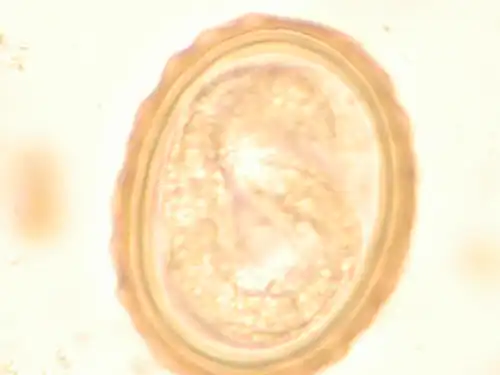

The larva of Ascaris lumbricoides developing in the egg -

Ascaris egg, incubation process: The Ascaris egg incubation process consists of placing the egg in a controlled environment, at 26 °C (79 °F) during 28 days, in acidic conditions. This process allows for the evaluation of an egg to determine if it is viable or not.

Most diagnoses are made by identifying the appearance of the worm or eggs in feces. Due to the large quantity of eggs laid, diagnosis can generally be made using only one or two fecal smears.[33] The diagnosis is usually incidental when the host passes a worm in the stool or vomit. The eggs can be seen in a smear of fresh feces examined on a glass slide under a microscope and there are various techniques to concentrate them first or increase their visibility, such as the ether sedimentation method or the Kato technique. The eggs have a characteristic shape: they are oval with a thick, mamillated shell (covered with rounded mounds or lumps), measuring 35–50 micrometer in diameter and 40–70 in length. During pulmonary disease, larvae may be found in fluids aspirated from the lungs. White blood cell counts may demonstrate peripheral eosinophilia; this is common in many parasitic infections and is not specific to ascariasis. On X-ray, 15–35 cm long filling defects, sometimes with a whirled appearance (bolus of worms).